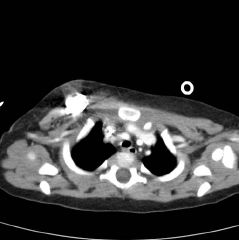

P.I= مشکل کودک از 50 روزگی شروع شده است. که با انجام

آزمایش ادرار

(U/A)

متوجه وجود هماچوری میکروسکوپی(30-35 گلبول قرمز) می شوند. علت انجام آنالیز ادراری

، این بوده که در سونوی 4 بعدی مادر در ماه هشتم حاملگی تورم در کلیه راست جنین

مشاهده شده بود. سونوگرافی در 50 روزگی نرمال بوده است. در 2 ماهگی هماچوری گروس هم

ایجاد می شود واز آن موقع تا کنون هماچوری میکروسکوپی ادامه داشته و هماچوری گروس

هم گاها دیده شده است.

در 2 ماهگی دفع پروتئین در ادرار در حد 2+ ایجاد می شود. تا 6 ماهگی هماچوری ادامه

می یابد و با انجام آزمایش پیگیری می شود.

یابد و با توجه به هماچوری و سایر علایم در تاریخ 12/2/88 بیوپسی کلیه انجام می

شود. در زمانی که برای بیوپسی کلیه بستری می شود ، یکسری ضایعات پوستی ماکولر هم

روی بدن ایجاد می شود.

جواب بیوپسی کلیه بیمارستان مفید:

Minimal mesengeal proliferation and focal glomerular sclerosis

Comment:in spite of absence of light microscopic positive findings membranous

lupus nephritis should be ruled out by EM and follow up the patient

جواب میکروسکپ الکترونی بیمارستان بقیه الله:

Thin glomerular basement membrane disease